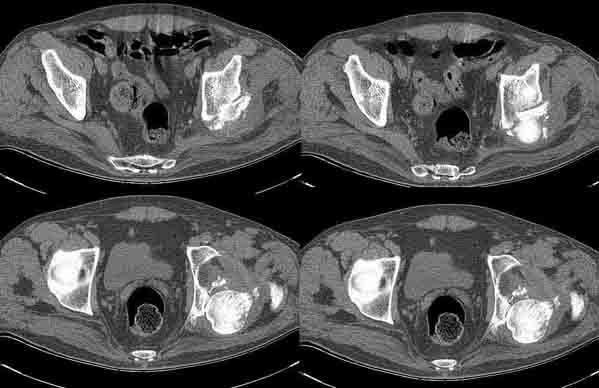

Больной Н. 54 лет. Поступил в подвздошным вывихом левого бедра. После попытки закрытого одномомендного вправления 2 мес. на скелетном вытяжении. На Rg контроле видимость вправления, на КТ - неустраненный вывих. По причине тяжелой соматической патологии открытое вправление и репозицию заднего края выполнить не представляется возможным. Вправление аппаратом внешней фиксации, КТ - этапах вправления - дефект заднего края. Что вы нам посоветуете по дальнейшей тактике? Больной Н. 54 лет. Диагноз: Закрытый оскольчатый перелом заднего края вертлужной впадины слева, подвздошный вывих левого бедра. Ушиб грудной клетки. ИБС. Стенокардия напряжения. ФКI-II. Постинфарктный кардиосклероз. Артериальная гипертония II степени, риск IV. НI. Состояние после аорто-коронарного шунтирования. Хронический бронхит. ДНI.Травма в результате ДТП. Больной лечился консервативно - закрытое одномоментное ручное вправление, фиксация скелетным вытяжением в течение 2 месяцев. На контрольных обзорных рентгенограммах таза в динамике: головка бедра располагается в проекции вертлужной впадины, суставные поверхности конгруентны. После снятия скелетного вытяжения выполнялся КТ - контроль тазобедренного сустава, на котором обнаружен неустраненный задний вывих бедра. Через 2 месяца наложена передняя тазовая и бедренная опоры. По причине тяжелого соматического состояния не представлялось возможным выполнить открытое вправление вывиха и остеосинтез заднего края. Представлен КТ- контроль на этапе вправления, на котором виден дефект заднего края вертлужной впадины.

Целесообразно готовить на протезирование, если это реально по общему состоянию или выждать время до нормализации общего состояния (3-6 месяцев). Такой дефет заднего края (по представленным КТ) позволяет достаточно стабильно имплантировать впадину на цемент, но с медиализацией имплантационного ложа до второго кортикала. Свод, большая часть заднего и передний края целые.

Да, есть дефект заднего края и, похоже, внутрисуставные тела, хотя снимки оставляют желать лучшего. Вопрос об операбельности серьезный, конечно. Но учитывая то, каким отягощенным пациентам сейчас выполняется даже эндопротезирование тазобедренного сустава, возможно, в данном случае поторопились с заключением о невозможности операции?